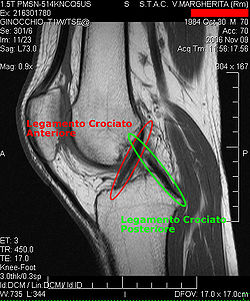

Procédés d'imagerie

Le diagnostic peut être confirmé par imagerie (IRM). Mais il faut noter que l'interprétation de l'IRM seule pour le diagnostic de rupture de LC conduit à 20 % de faux diagnostics. Cela dépend des images de coupe et de la position appropriée du genou pendant l'IRM. Le radiologue doit connaître avec précision les circonstances qui ont conduit à la blessure, et avoir aussi une bonne expérience de l'étude d'une articulation blessée, pour éviter les faux diagnostics. Pour comparer avec l'IRM, le taux d'erreur du test de Lachman, bien plus simple à accomplir, n'est que de 10 %[106],[107],[108],[109]. L'IRM est donc généralement moins sensible et moins spécifique que l'examen clinique par un orthopédiste qualifié[110]. Le résultat de l'IRM n'a que relativement rarement une influence sur la formulation finale du diagnostic[111] et ne devrait pas servir de remplacement pour une anamnèse soigneuse et la palpation[112]. Plusieurs études arrivent à la conclusion que l'IRM n'a de sens que pour des blessures complexes difficiles à expliquer, et là, pour éviter de poser un diagnostic négatif[113],[114],[115].